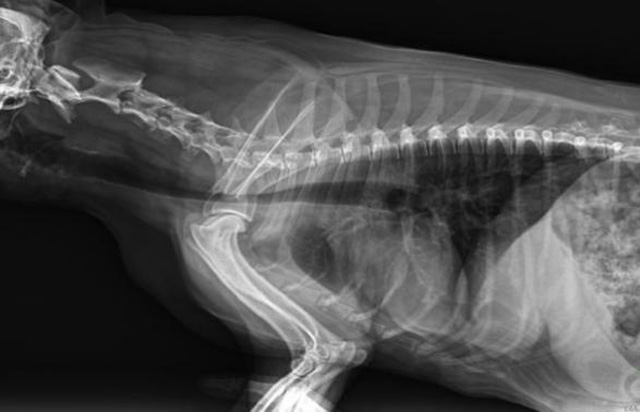

寵物DR是動物專用的數字化攝影係統,x線的穿透能力、低的輻射劑量,輻射劑量比X光低:熒光作用和感光作用,可以穿透動物身體的結構顯示成像,動物的各個部位成像輔助獸醫診療。寵物DR采集時間10ms以下,成像時間僅為3秒,從檢查到出診斷報告大約5—10分鍾。較高的空間分辨力和低噪聲率,可獲得高清晰圖像。 DR成像數字化處理的特點可進行後處理。提高了病灶的檢出率,這樣大大提高檢查的準確率提高診斷準確率避免漏診誤診等情況。